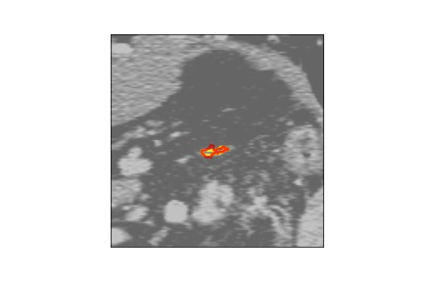

The human annotations are imperfect, especially when produced by junior practitioners. Multi-expert consensus is usually regarded as golden standard, while this annotation protocol is too expensive to implement in many real-world projects. In this study, we propose a method to refine human annotation, named Neural Annotation Refinement (NeAR). It is based on a learnable implicit function, which decodes a latent vector into represented shape. By integrating the appearance as an input of implicit functions, the appearance-aware NeAR fixes the annotation artefacts. Our method is demonstrated on the application of adrenal gland analysis. We first show that the NeAR can repair distorted golden standards on a public adrenal gland segmentation dataset. Besides, we develop a new Adrenal gLand ANalysis (ALAN) dataset with the proposed NeAR, where each case consists of a 3D shape of adrenal gland and its diagnosis label (normal vs. abnormal) assigned by experts. We show that models trained on the shapes repaired by the NeAR can diagnose adrenal glands better than the original ones. The ALAN dataset will be open-source, with 1,594 shapes for adrenal gland diagnosis, which serves as a new benchmark for medical shape analysis. Code and dataset are available at https://github.com/M3DV/NeAR.